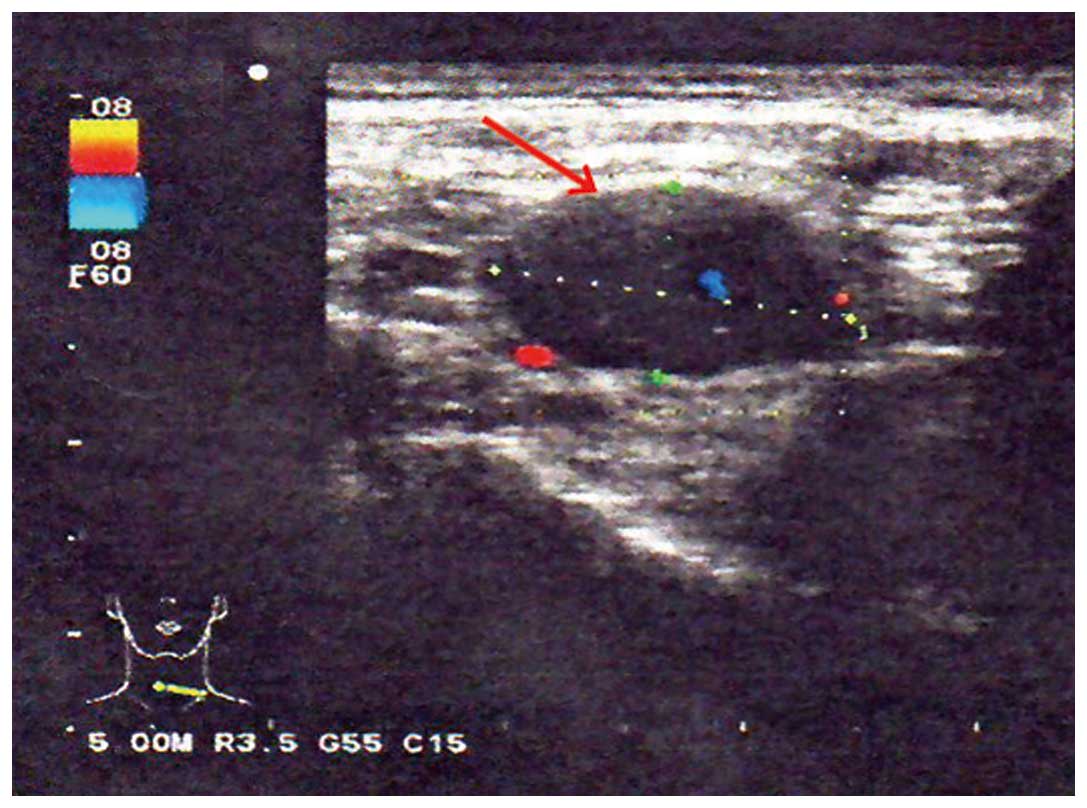

Figure 2.

Ultrasound of the right cervical lymph nodes (arrow).

A neurological examination revealed proximal muscle weakness and absence of deep tendon reflexes. The cranial nerve, cerebellar and sensory functions were all normal. The laboratory tests revealed hyponatremia and hypochloremia. The electromyogram suggested neurogenic damage (Bilateral abductor muscle and peroneus longus, potential loss of the median nerve, the common peroneal nerve, and mild slowing of the motor conduction velocity of the tibial nerve). A repetitive nerve stimulation test performed on the right median nerve revealed a decremental response to the electrical stimulation. An experiment with neostigmine supported the presence of postsynaptic membrane lesions. Repeated nerve stimulation of 7 Hz lead to an increased response, whereas repeated nerve stimulation of 15 Hz was associated with decreased response (Fig. 1). The findings of magnetic resonance imaging scans of the brain and lumbar vertebra were normal. The preliminary diagnosis of the patient's condition was MG. However, treatment with hypertonic saline and fluid restriction, as well as low-dose corticosteroid therapy for MG, did not improve the symptoms. After referring to several studies in the literature (6–8), LEMS was taken into consideration. The levels of tumor markers, including carcinoembryonic antigen and neuron-specific enolase, were found to be abnormal. An ultrasound of the superficial lymph nodes identified an enlarged lymph node in the right cervical region, sized 1.5×0.9 cm (Fig. 2). Chest computed tomography (CT) images revealed a 1.6-cm mass in the superior lobe of the right lung, associated with a small amount of pleural effusion (Fig. 3). A right cervical lymph node biopsy was conducted; on pathological immunohistochemical examination, the lesion was found to be positive for epithelial membrane antigen (+), CD56 (+), thyroid transcription factor-1 (+), creatine phosphokinase (+) and Ki67 (+++) and negative for synaptophysin and leukocyte common antigen. Combined with the findings of the histopathological analysis (hematoxylin and eosin staining; Fig. 4), the diagnosis was eventually confirmed as SCLC combined with LEMS.